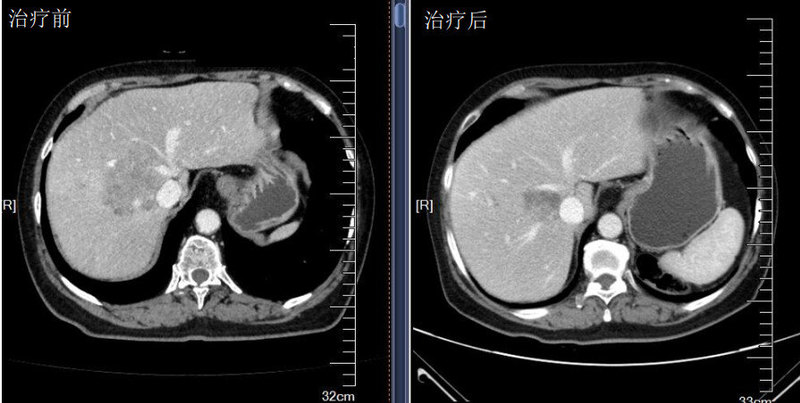

治療前 一位晚期腸癌、腹腔腹膜廣泛轉(zhuǎn)移的病人,一線標(biāo)準(zhǔn)治療原發(fā)性耐藥,病情進(jìn)展迅速,屬于臨床難治性腫瘤,常規(guī)二線治療有效率低,如果病情再不能得到控制,患者將沒有后續(xù)治療的機會,因此我們遵循指南原則但沒有窠臼于指南,結(jié)合最新的臨床研究進(jìn)展,將免疫治療(PD-1抗體)和小分子抗血管TKI治療前移,并配合化療。 治療后 治療后2月 患者經(jīng)過一個療程治療后患者臨床癥狀顯著緩解,三個療程后基本達(dá)到完全緩解,影像學(xué)基本上看不到腫瘤了。創(chuàng)新治療對于疑難腫瘤來說,不但是方法的更新,重要的是理念的前進(jìn),對患者而言是更多機會。